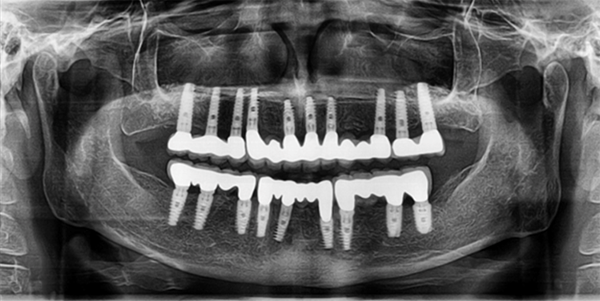

img3 img4

Fixed supported full mouth rehabilitation

From the final prosthesis prospective:

3. Implant supported full mouth rehabilitation